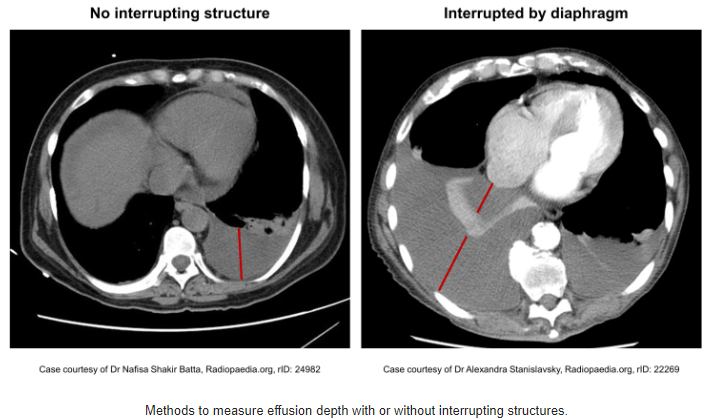

Pleural Effusion>